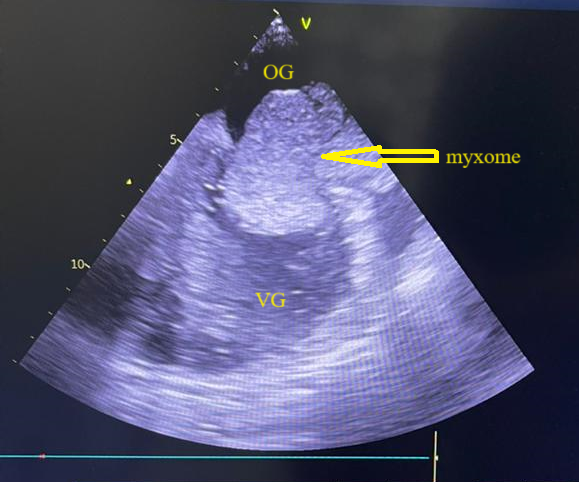

Figure 3 (a et b) : Echocardiographie transthoracique en mode bi dimensionnel montrant le myxome de l’oreillette gauche appendu au septum inter atrial vu en mode 4 cavités (a) et 2 cavités (b) chez un patient de 54 ans (Cas clinique n°2). VG= ventricule gauche; OG= oreillette gauche; OD= oreillette droite ; VD= ventricule droit.

(a)

(b)

Figure 4 (a et b): Echocardiographie transoesophagienne en bi dimensionnelle, incidence 4 cavités plan oblique à 135° montrant un myxome appendu au septum inter atrial (Cas clinique n°2). VG= ventricule gauche ; OG= oreillette gauche ; VD= ventricule droit.